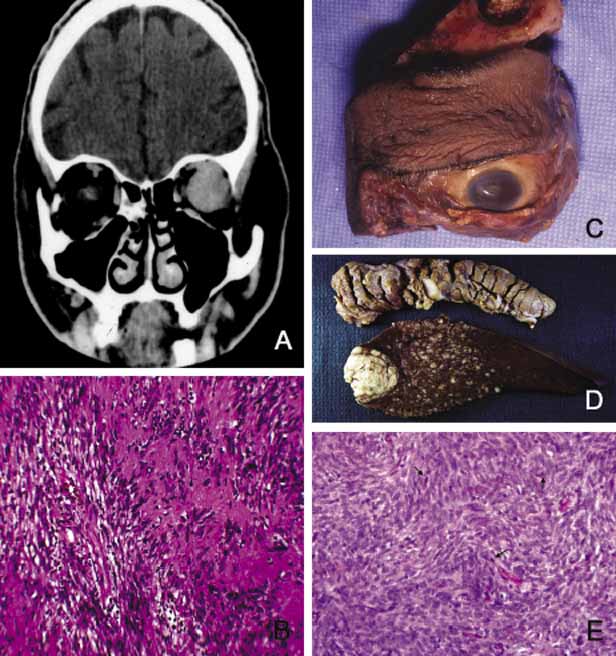

Cavernous hemangioma is another benign vascular tumor that occurs in adults, usually as a solitary, unilateral lesion, but multiple tumors have been described.185,186 Unlike capillary hemangioma it is not associated with other lesions elsewhere in the body. It is usually located within the muscle cone but may also be seen in extraconal locations and presents with slowly progressive proptosis without too much extraocular motility disturbance (Fig. 18). Gross appearance of cavernous hemangioma is a well encapsulated reddish purple lesion with a sponge-like consistency on its cut surface. Histopathologically, it consists of dilated vascular channels lined by endothelium and smooth muscle and intervening fibrous stroma. The endothelial cells are held together by tight junctions and display basement membrane reduction. Clinical differential diagnosis of cavernous hemangioma on imaging include fibrous histiocytoma, hemangiopericytoma, schwannoma and metastatic tumors.187 Surgical removal of the tumor is the treatment of choice.

Fig. 18 Cavernous hemangioma. Despite the presence of a large intraconal tumor in T1-weighted axial MRI, the left globe shows minimal proptosis because of the slowly growing nature of the tumor. This tumor was compressing onto the optic nerve to cause significant papilledema but the patient did not have any extraocular motility disturbance. The gross photograph of the transverse section of the well encapsulated cavernous hemangioma shows multiple loculations of the tumor. Histopathologically the Masson trichome stain demonstrates numerous caverns surrounded by thin fibrous septal, containing clusters of red blood cells. The arrow points to the capsule of the neoplasm. Note that some of the orbital fat is in fact within the fibrous tissues of the tumor (arrowheads).

Another lesion of this category that presents with large cavern formations surrounded by different amounts of fibrous tissue is lymphangioma.188–190 Unlike cavernous hemangioma, however, the space formations in this lesion are not lined by endothelial cells and do not contain vascular smooth muscle; the spaces are lined by flat mesothelial-like cells (Fig. 19). Spontaneous bleeding may take place within these cystic spaces resulting in “chocolate” cysts. In one-third of the cases, lymphoid follicles with germinal centers may be present in the intervening fibrous stroma and some tumors with abundant lymphoid tissue may respond to systemic steroid treatment. Because of the infiltrating nature of this tumor, surgery is not an early option of management; these lesions should be managed conservatively.190

Fig. 19 Lymphangioma. A 23-year-old woman with marked axial proptosis of the left eye secondary to lymphangioma (A). The tumor is depicted in the T1-weighted axial MRI showing a multiloculated tumor with marked enhancement occupying the entire orbit (B). Frame C shows multiple irregular lymphatic spaces (ls) that were changing in size and shape during the B-scan ultrasonography. The histopathology of the same case (D, E) reveals multiple lymphatic spaces (ls) lined by flat mesothelial-like cells surrounded with irregular fibroconnective tissue and lymphoid follicles with germinal centers (g). Note that some of the lymphatic spaces are filled totally or partially with blood.

Orbital varix is another orbital vascular lesion that develops as a distention of a venous channel leading to stagnant blood flow resulting in thrombus formation.191 Orbital varices are divided into primary lesions, confined to the orbit and secondary lesions associated with intraorbital and intracranial arteriovenous malformations.54 Vascular hamartomatous lesions may contain arteriovenous malformations with or without abnormal communication between arterial and venous vasculature. These lesions should not be confused with carotid cavernous and dural cavernous fistulas, which affect the orbit secondarily.192 If one clinically suspects an A-V malformation component in an orbital vascular lesion, CT angiogram and arterial and venous angiograms should be used to rule out the connection of the lesion to systemic circulation.193 Color Doppler flow imaging has also been used to examine these tumors. In addition to the above detailed vascular tumors, angiosarcoma, Kaposi sarcoma, intravascular papillary endothelial hyperplasia (IPEH), vascular leiomyoma and angiolymphoid hyperplasia with eosinophilia (Kimura disease), can rarely be encountered in the orbit.194–198

In this chapter, neural neoplasms are covered under two major groups: tumors originating from central nervous system (CNS) tissues, and tumors originating from peripheral nerves.